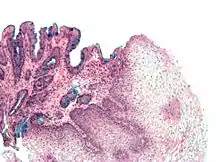

Microscopic Anatomy

The basic layout pattern holds true in the stomach, although the stomach has a third inner layer of oblique muscle fibers. The mucosal layer has numerous pits opening into the lumen, the mouths of the gastric glands. Some of these glands penetrate down into the submucosal layer.

Gastric Glands

The gastric glands secrete mucous, hydrochloric acid and enzymes into the stomach. They are located for the most part in the mucosal layer of the stomach, but some of the deeper gland penetrate into the submucosal layer, and secrete into the lumen via ducts. Several different secretory cells are found: mucous; parietal; chief cells; D cells; enterochafin cells; and G cells.

Mucous cells secrete both mucous and bicarbonate, substances that protect the stomach from auto-digestion. Parietal cells secrete hydrochloric acid (1-3 liters a day) which cause the pH in the stomach to fall as low as 1. Chief cells secrete the enzyme pepsinogen, which is activated to pepsin by the pH of the stomach. G cells produce gastrin, a hormone that promotes gastric acid secretions and stimulates the growth of the gastric mucosa.

The composition of the gastric glands varies throughout the stomach. In the fundus, the glands are more branched and contain all the different kinds of secretory cells. In the pyloric part of the stomach the glands are deeper and contain more mucous cells. Chief cells are found only in the fundus of the stomach, G cells are found mainly in the antrum, and the other cells are found in all areas.